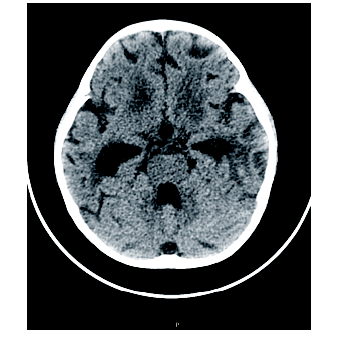

周正根(影像科主治医师):根据患儿的影像学图片介绍一下TBM的影像学特点, 首先, TBM比较容易出现脑积水, 见图1, 在脑底部的脑池可见分泌物, 脑室壁增厚; 其次, 脑室、脑沟可见到钙化, 见图2和图3, 钙化灶对结核的诊断有一定意义; 第三, 由于TBM可能侵犯到小血管, 所以可以见到一些低密度的梗塞病灶。

患儿确诊TBM, 治疗上继续三联抗结核治疗及鞘注抗结核药物。但后续治疗过程中患儿再次出现呕吐, 伴右侧肢体抖动、意识改变、双侧瞳孔不等大, 神志淡漠, 头颅CT平扫检查提示交通性脑积水, 双侧基底节区及左侧额叶、右侧顶叶皮层低密度灶, 考虑梗塞可能性大。遂予床边行颅骨钻孔脑室外引流术。并予甘露醇脱水减轻脑水肿。后患儿病情好转后转到胸科医院进一步专科抗结核治疗, 其间因脑积水在我院反复行左右脑室钻孔引流术, 最终行左侧脑室腹腔引流术。后患儿病情好转、稳定, 复查骨髓为完全缓解, MRD检测未见残留。遂按照GD2008广东协作组方案再次化疗, 并继续三联抗结核治疗, 其间多次查脑脊液TB-DNA定量水平均正常(10拷贝)。